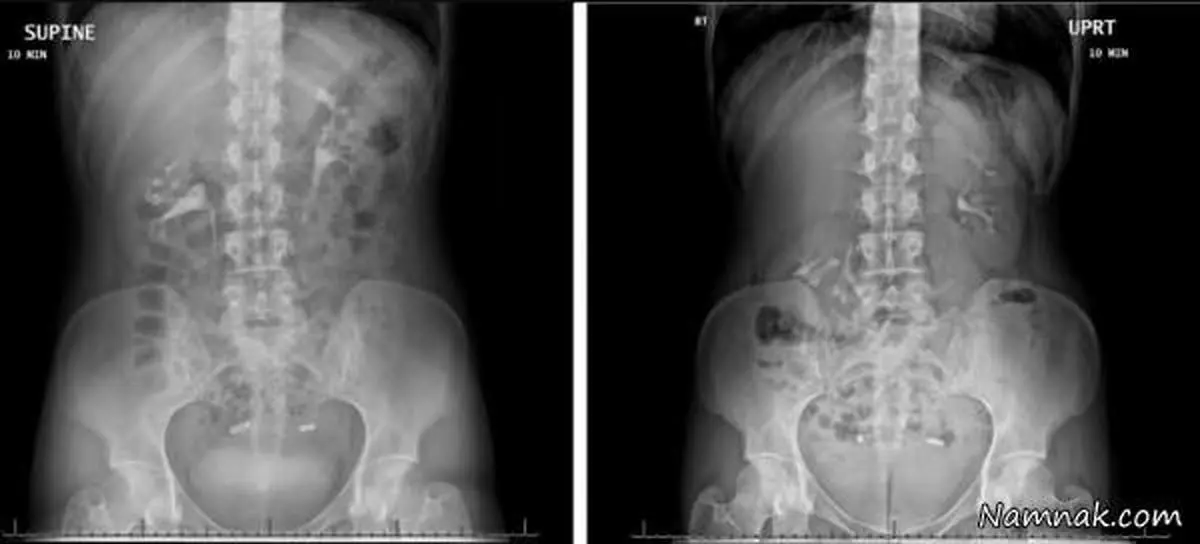

هنگامی که اسکن در نهایت از کلیه زنان بطور ایستاده و دراز کشیده ،صورت گرفت تصاویر نشان دادند کلیه راست او هنگامی که ایستاده بود به سمت لگن حرکت کرده بود که این امر تشخیص کلیه متحرک را تایید کرد.

نویسنده گزارش دکتر آکشای سود ، اورولوژیست در بیمارستان هنری فورد در دیترویت  گفت :کلیه شناور یا " سرگردان - متحرک " از نظر پزشکی به عنوان پتوز کلیه شناخته شده " وضعیتی است که در آن یکی از کلیه ها زمانی که فرد می ایستد به لگن وارد می شود که به این شرایط افتادگ کلیه نیز گفته می شود . دراین حالت ، کلیه راست زنان بیش از 2 اینچ ( تقریبا 6 سانتی متر ) و یا طول دو مهره، زمانی که حالت خود را از دراز کشیدن به ایستادن تغییر می دهند پایین می آید .

طبق گزارشات این زن 28 ساله شرایط نادری داشت که به عنوان کلیه شناور شناخته می شد. تقریبا شش سال بود که درد شکمی را در سمت راست خود تجربه می کرد وقتی او می ایستاد حالش بدتر اما وقتی دراز می کشید حالش بهترمی شد . او همچنین به پزشکان گفت که درد دراواخر دوران بارداری کاهش یافته است.